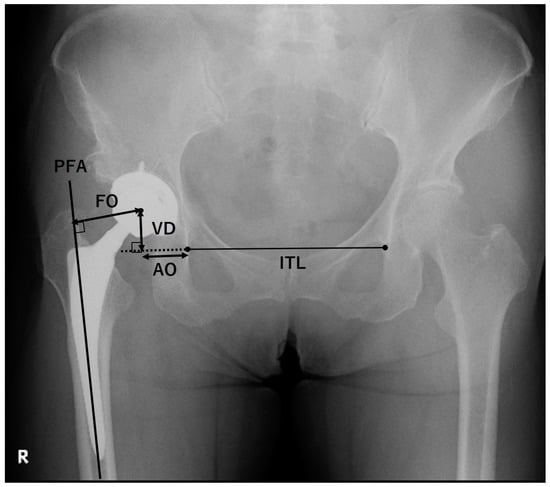

Radiographic evaluations were performed on AP and cross-table lateral (CL) radiographs obtained pre-THA and at the final follow-up. The AP radiographs were taken in the supine position with a standardized tube-to-film distance (120 cm) and perpendicular orientation of the tube to the table. The CL radiographs were obtained with the contralateral hip flexed at 90°. The X-ray beam was parallel to the examination table and 45° cranial to the long axis of the trunk. The film was set perpendicular to the examination table using a film holder. The cup inclination and anteversion were measured on the AP and CL radiographs at 1 week after THA. The hip joint center, AO, vertical distance (VD), and FO were measured on the AP radiographs at 1 week after THA (Figure 2). The AO was measured as the horizontal distance from the inferior edge of the teardrop to the point where an extension of the interteardrop line (ITL), connecting the inferior edges of both teardrops, intersects with a perpendicular line from the hip joint center []. The VD was measured as the distance from the hip joint center to the point where the extension of the ITL intersects with the perpendicular line from the hip joint center []. The FO was measured as the distance from the hip joint center to the intersection with the proximal femoral shaft axis []. GO was measured as the sum of FO and AO. The Crowe classification [] was evaluated on the AP radiographs before THA. Cup stability was evaluated using McPherson’s criteria []: grade IA, no radiolucency; grade IB, one zone of radiolucency; grade IC, two zones of radiolucency; grade II, complete radiolucent line of <2 mm in all zones; grade III, progressive radiolucent line at zone III, complete radiolucent line of ≥2 mm in all zones, or cup migration. Stem stability was evaluated using Engh’s criteria []: fixation by bone ingrowth, no subsidence and minimal or no radiopaque lines around the stem; stable fibrous fixation, no progressive migration and extensive radiopaque lines around the stem of ≤1 mm; unstable, progressive subsidence or migration; and at least partially surrounded by divergent radiopaque lines.

Figure 2.

Radiographic indices measured on the anteroposterior radiographs. The interteardrop line (ITL) connects the inferior edges of both teardrops. The acetabular offset (AO) was measured as the horizontal distance from the inferior edge of the teardrop to the point where an extension of the ITL intersects with a perpendicular line drawn from the hip joint center. The vertical distance (VD) was measured as the distance from the hip joint center to the point where the extension of the ITL intersects with the perpendicular line from the hip joint center. The femoral offset (FO) was measured as the distance from the hip joint center to the intersection with the proximal femoral shaft axis (PFA). The global offset was measured as the sum of FO and AO.